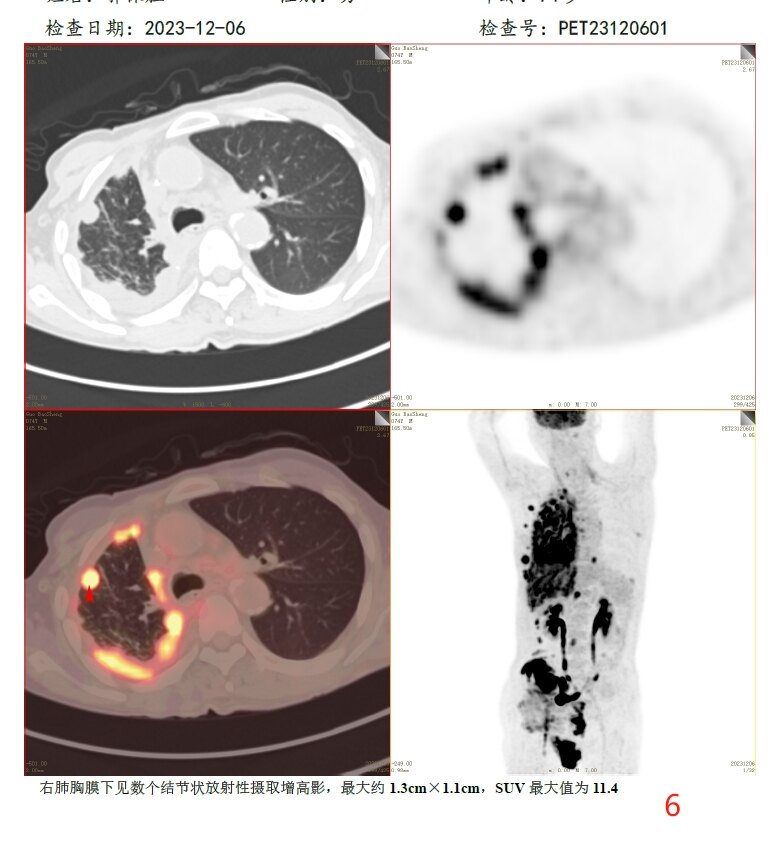

放疗前PET/CT(2023-12-06):

病变层面:

6